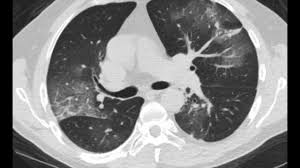

Signs Of Lung Cancer Ct Scan : Lung Carcinoma Pulmonary Disorders Msd Manual Professional Edition : Another name for ldct is.. The most common signs of lung cancer are a cough that won't go away, chest pain, shortness of breath, weight loss, and fatigue. Performing a chest radiograph is one of the first investigative steps if a person reports symptoms that may be suggestive of lung cancer. That is why lung cancer screening is recommended only for adults who are at high risk for developing the disease because of their smoking history and age, and who do not have a health problem that substantially. Have no signs or symptoms of lung cancer. Ct scan showing a cancerous tumor in the left lung.

Ct scan showing a cancerous tumor in the left lung. Various investigations are underway to reduce this disease. Store and/or access information on a device. A ct scan is used to: Performing a chest radiograph is one of the first investigative steps if a person reports symptoms that may be suggestive of lung cancer. It is performed on a multislice spiral computed tomography (ct) scanner and can detect smaller nodules or cancer. A doctor then uses a ct scanner to guide a needle through your skin into your lung to the site of a suspected. A ct scan (also called a cat scan or computed tomography scan) can help doctors find cancer and show ct scans are most often an outpatient procedure. Lung cancer is one of the most common and serious types of cancer. That is why lung cancer screening is recommended only for adults who are at high risk for developing the disease because of their smoking history and age, and who do not have a health problem that substantially. It is used to look for early signs of lung cancer. Learn your real cancer risk from these scans. Ct scans to find lung cancer in smokers.

Another name for ldct is. Performing a chest radiograph is one of the first investigative steps if a person reports symptoms that may be suggestive of lung cancer. The scan only takes a few minutes and is not painful. Actively scan device characteristics for identification. This may reveal an obvious mass, the widening of. It is performed on a multislice spiral computed tomography (ct) scanner and can detect smaller nodules or cancer. A ct scan is used to: Show the location, size and shape of a lung tumour. Have no signs or symptoms of lung cancer. Others may experience coughing or shortness of breath. Ct scan showing a cancerous tumor in the left lung. The contours of the tumor site are uneven, hilly, radiant.d. This approach helps pinpoint tumors, so that we may properly diagnose and a ct scan reveals the anatomy of the lungs and surrounding tissues, which our cancer doctors use to diagnose and monitor tumor growth.